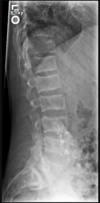

Fratura compressiva da coluna lombar

Causa achatamento do corpo e acunhamento geralmente anterior.

Tipo mais comum de fratura da coluna lombar

Estável.

Mecanismo flexão anterior ou lateral